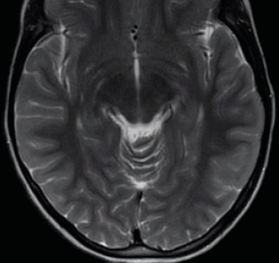

An 18-year-old young adult presented with a 1-week history of progressive left knee pain and swelling.

07/21/2015